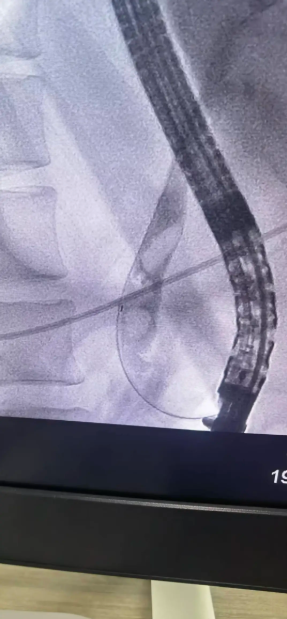

· 巧妙取石: 造影显示,患者胆总管下端有3颗直径约1.5cm的嵌顿性结石。专家采用球囊扩张、网篮取石等一系列高精尖技术,成功将结石完整取出,瞬间,淤积的胆汁顺利引流通畅。

· 鼻胆管引流: 为充分引流、控制感染,术中顺利放置了鼻胆引流管。整个手术流程如行云流水,仅用时不到半小时的时间便宣告成功。患者生命体征平稳,梗阻即刻解除。